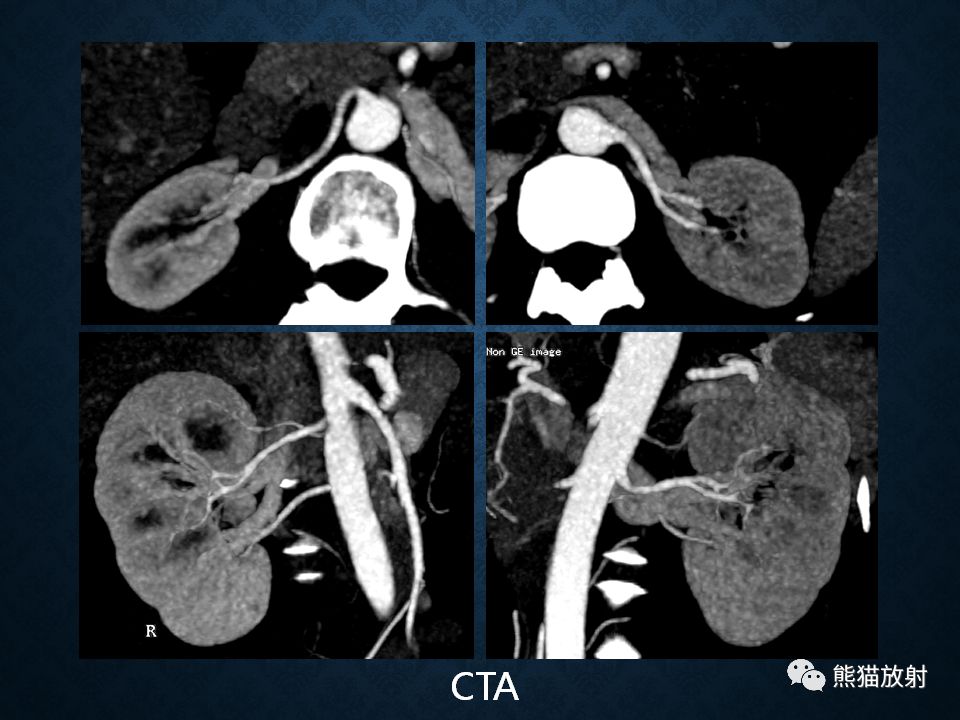

肾上腺常见肿瘤影像诊断